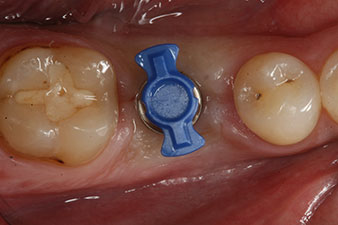

SmartPeg

Fig. 4: SmartPeg measuring posts screwed on to measure the implant stability quotients with the integrated W&H Osstell ISQ module.

The torque used for the machine-driven placement was 43 Ncm. In addition, after screwing a measuring post (SmartPeg) specially matched to the implant, the ISQ value was measured with the probe of the W&H Osstell ISQ module.